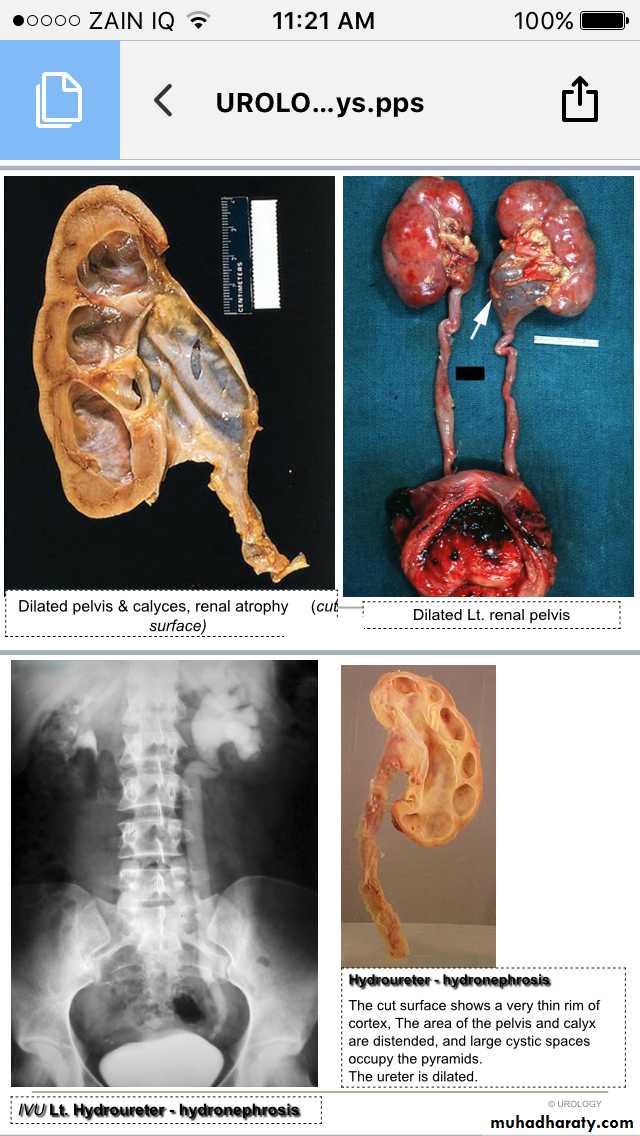

Hydronephrosis-Hydroureter

IVU